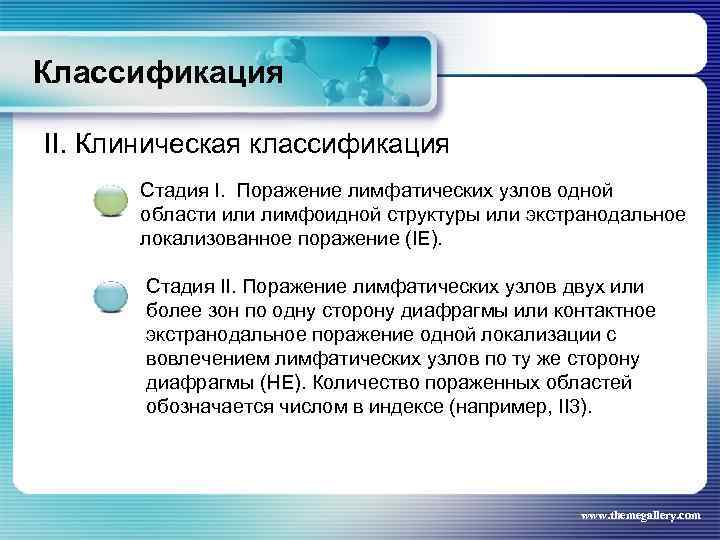

Классификация II. Клиническая классификация Стадия I. Поражение лимфатических узлов одной области или лимфоидной структуры или экстранодальное локализованное поражение (IE). Стадия II. Поражение лимфатических узлов двух или более зон по одну сторону диафрагмы или контактное экстранодальное поражение одной локализации с вовлечением лимфатических узлов по ту же сторону диафрагмы (НЕ). Количество пораженных областей обозначается числом в индексе (например, II 3). www. themegallery. com

Классификация II. Клиническая классификация Стадия I. Поражение лимфатических узлов одной области или лимфоидной структуры или экстранодальное локализованное поражение (IE). Стадия II. Поражение лимфатических узлов двух или более зон по одну сторону диафрагмы или контактное экстранодальное поражение одной локализации с вовлечением лимфатических узлов по ту же сторону диафрагмы (НЕ). Количество пораженных областей обозначается числом в индексе (например, II 3). www. themegallery. com